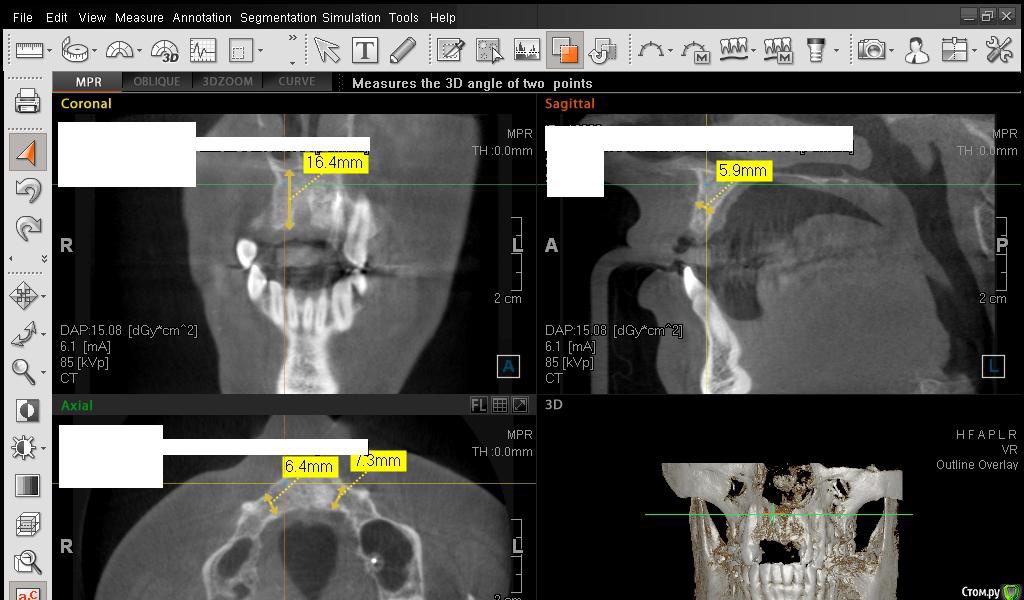

SDC Опубликовано 1 марта, 2015 Поделиться Опубликовано 1 марта, 2015 Сестричка, в левом верхнем углу КТ есть инструмент, обозначен, как линейка.С помощью ее необходимо провести замеры альвеолярного отростка на КТ вертикально и горизонтально.Для увеличения объема десны используются различные трансплантаты, но пока лучше аутотрансплантата (собственной десны с неба) ничего нет. Ссылка на комментарий

Сестричка Опубликовано 2 марта, 2015 Автор Поделиться Опубликовано 2 марта, 2015 Сделала замеры, надеюсь правильно? Старалась измерить наиболее уязвимые и тонкие места. Изначально планировались размеры имплантов 3 мм на 11 мм длиной. Смогут ли они туда встать? Ссылка на комментарий

SDC Опубликовано 2 марта, 2015 Поделиться Опубликовано 2 марта, 2015 Интересны размеры беззубого альвеолярного отростка на самой вершине его или рядом с вершиной на расстоянии 1 мм. от нее в проекции будущего местоположения имплантатов.Желательно размеры проводить рядом с объектом (как в черчении)По-моему, диаметр 3 мм. подходит для имплантации без костной пластики, но без трансплантации десны, одномоментно с имплантацией, не обойтись. 1 Ссылка на комментарий